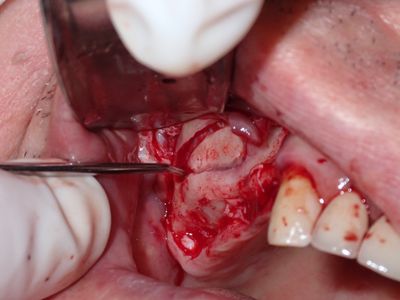

JGolos - R Sinus Augmentation

Very limited bone. window prepared with rotary and piezo electric instrumentation. no evidence of sinus membrane perforation, 1st layer: collatape 2nd layer: 80/20 mix of mineralized cortical/xenograft, membrane placed in internal aspect of window, additional bone on buccal followed by membrane. Tension-free primary closure.